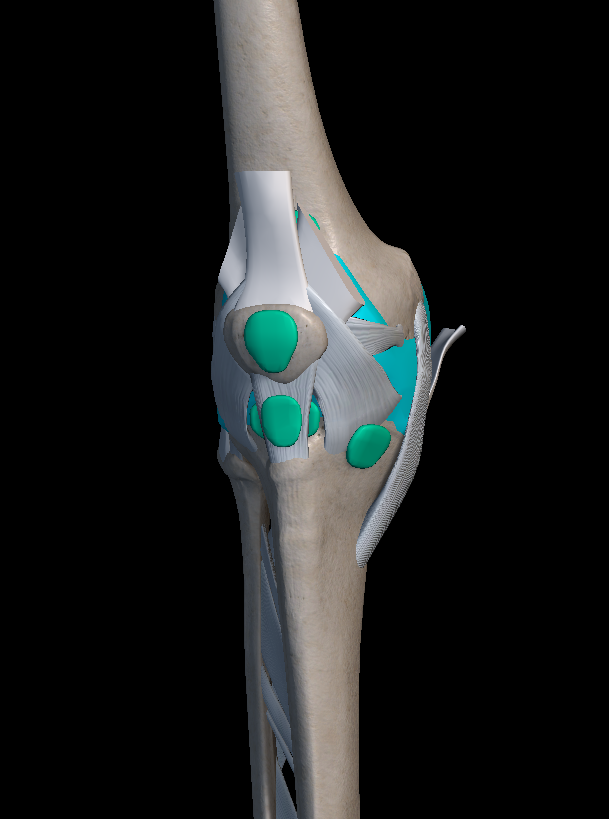

기본적으로 무릎 관절은 뼈와 뼈와 만나는 부위로서, 지면으로부터 오는 충격과 하중을 완화해주는 완충 작용을 하는 역할을 합니다. 그러나 종종 여러 가지 원인에 의해 무릎 관절에 염증이 나타나곤 하지요.

여러분들이 무릎에 염증이 발생하는 원인은 주로 무릎에 가해지는 반복적인 충격, 부상, 비만, 노화 등이 있습니다. 이러한 이유들로 인해 무릎 연골이 손상되고 관절 주변의 조직에서 염증 반응이 나타나게 되는 것이죠.